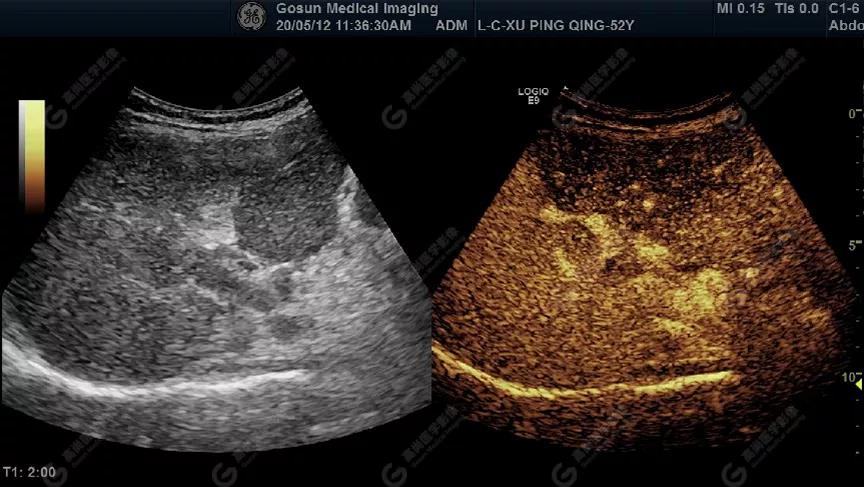

超聲造影顯示門靜脈內(nèi)低回聲呈高增強(qiáng)

延遲期肝S7局部回聲減低,范圍約82mm×50mm

內(nèi)見范圍約13mm×16mm低增強(qiáng)區(qū)

超聲所見肝包膜不光滑,實質(zhì)回聲增粗,不均勻,以右葉顯著,肝內(nèi)可見散在高回聲結(jié)節(jié),最大約7mm×5mm,邊界清,形態(tài)規(guī)則,CDFI顯示高回聲結(jié)節(jié)未見明顯異常血流信號。門靜脈主干內(nèi)徑約14mm,門靜脈右支管腔內(nèi)見實性低回聲,大小約23mm×14mm,邊界不清,形態(tài)不規(guī)則,局部與肝組織分界不清,CDFI:門靜脈主干血流緩慢,左支血流充盈好,右支血流充盈缺損,低回聲內(nèi)未見明顯血流信號。超聲造影:經(jīng)左側(cè)肘靜脈團(tuán)注超聲造影劑sonovue2.0ml。肝組織開始增強(qiáng)時間8秒,病灶開始增強(qiáng)時間11秒,邊界清晰。脈期呈均勻高增強(qiáng),至門脈期和延遲期消退為低增強(qiáng)。延遲期肝S7段局部回聲減低,范圍約82mm×50mm,內(nèi)見一低增強(qiáng)區(qū),范圍約13mm×16mm。